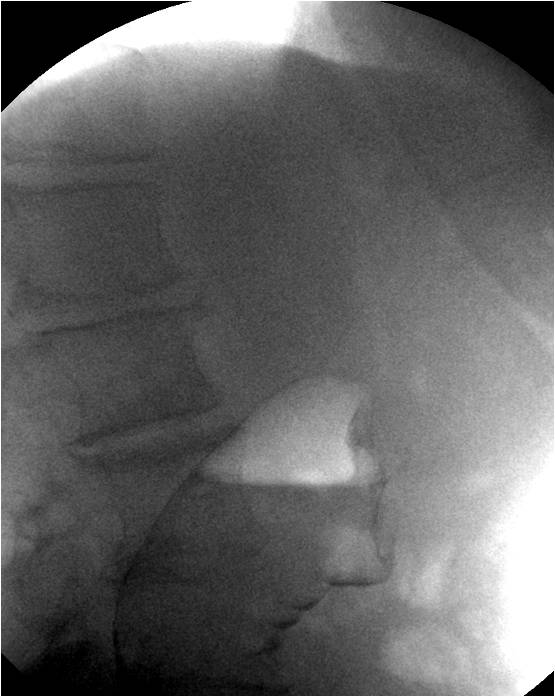

Рак слепой кишки - полициклические дефекты выполнения , тени самих опухолей.

Рак поперечной ободочной кишки справа (пневмоколонограмма - тень опухоли в просвете кишки, ассиметричное, практически полное сужение)